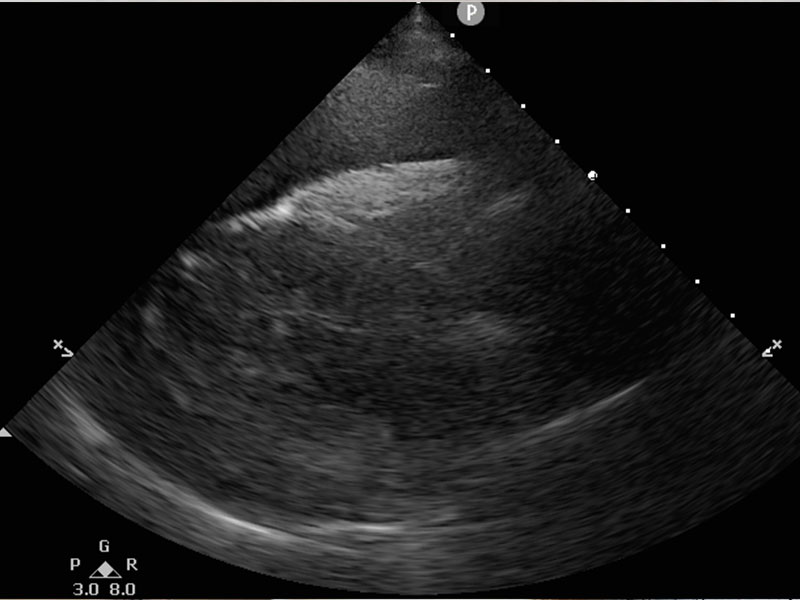

我們曾搶救呼吸困難的毛小孩,經檢查後發現是胸腔積液造成,因狀況緊急,便即刻進行手術,將胸水抽出及供氧處理,經由手術後,毛小孩的生命跡象才逐漸穩定;另一個案,主人形容毛小孩突然倒地,非常虛弱的樣子,我們馬上進行檢查,發現為心包囊積液症狀,經由手術處理後,毛小孩也逐漸恢復元氣。

圖為突然倒地虛弱的大狗美美,迅速安排檢查發現為心包囊積液導致不適。